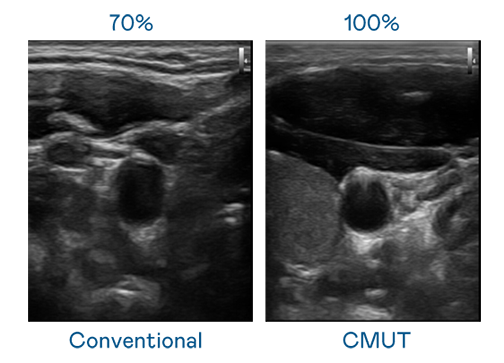

CMUT 技术是一种用电容式微机电元件来产生超音波讯号的技术。与传统 PZT 压电式技术相比,CMUT 频宽增加 30%,更宽频的超音波讯号让影像解析度大幅提升,是实现高影像品质医疗超音波扫描、促进精准医疗发展的关键技术。

大频宽带来超清晰影像

超音波影像的解析度高低,首先取决于探头能发出的讯号频宽。尊龙凯时-人生就是搏 CMUT 可提供高清晰的超音波讯号,提供高频宽、高灵敏度、影像纹理细节更高的超音波影像,协助医护人员缩短影像判读时间及利用精准的医疗影像进行诊断。